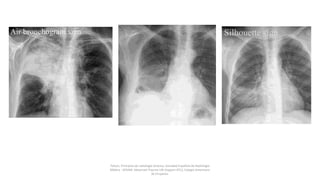

Parénquima pulmonar  Aumentosde densidad: • Patrón alveolar • Patrón intersticial • Masas y nódulos: o Nódulos: Lesión menor de 3 cm o Masa: Lesión mayor de 3 cm Interpretación de radiología de tórax Estructuras radiológicas: Felson, Principios de radiología torácica. Sociedad Española de Radiología Médica - SERAM. Advanced Trauma Life Support ATLS, Colegio Americano de Cirujanos.

Interpretación de radiología detórax Estructuras radiológicas: Parénquima pulmonar Felson, Principios de radiología torácica. Sociedad Española de Radiología Médica - SERAM. Advanced Trauma Life Support ATLS, Colegio Americano de Cirujanos.

Parénquima pulmonar Pérdida devolúmen Atelectasias Interpretación de radiología de tórax Estructuras radiológicas: Felson, Principios de radiología torácica. Sociedad Española de Radiología Médica - SERAM. Advanced Trauma Life Support ATLS, Colegio Americano de Cirujanos.